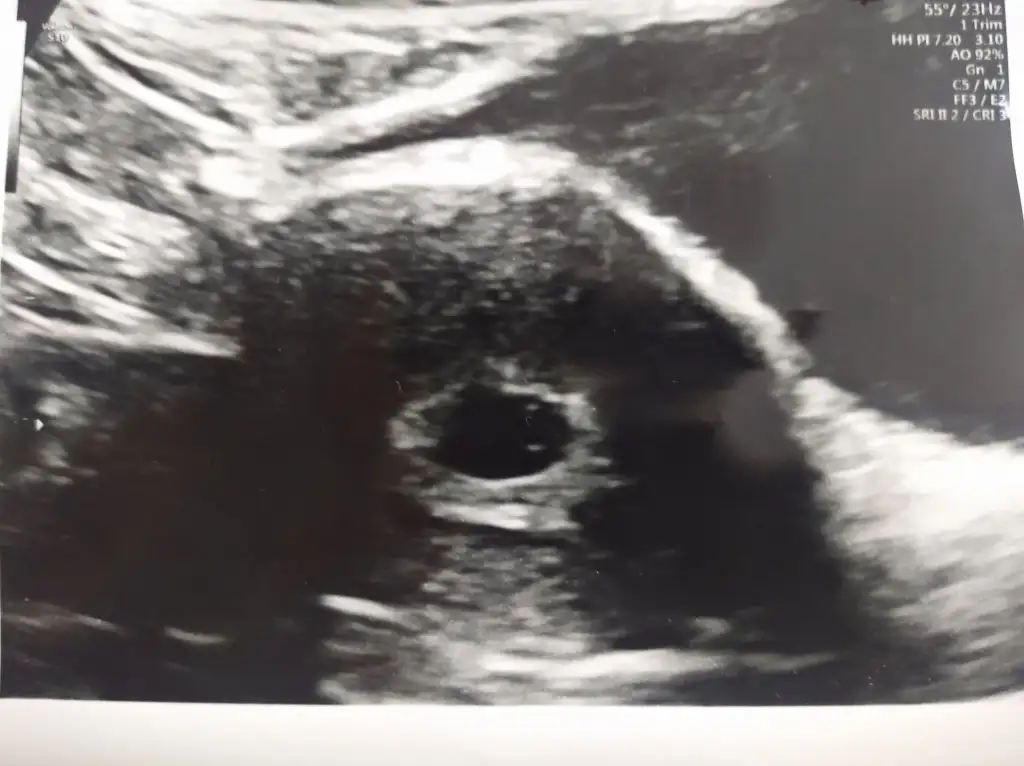

Hayirli olsun gozun aydinBugün bende keseyi ve bebeği gördüm çok şükür kabuslarin bı kısmını atlattım dış gebelik mi boş gebelik mi ömrümü yedi on gündür bugunumuze şükür Rabbim dileyen herkese tattirsin bu duyguları amin

Hadi tebrikler darısı sağlıkla kucağına almaya insallahUygulamada yüklenmiyormussiteden yükledim